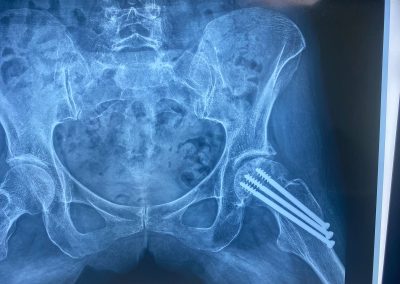

تم إجراء تثبيت داخلي لكسر بالحوض بمسامير عام ٢٠٠٩

في عام ٢٠٢١ بدأت تشعر بالام متزايدة بالمفصل كما بينت الاشعات تآكل به